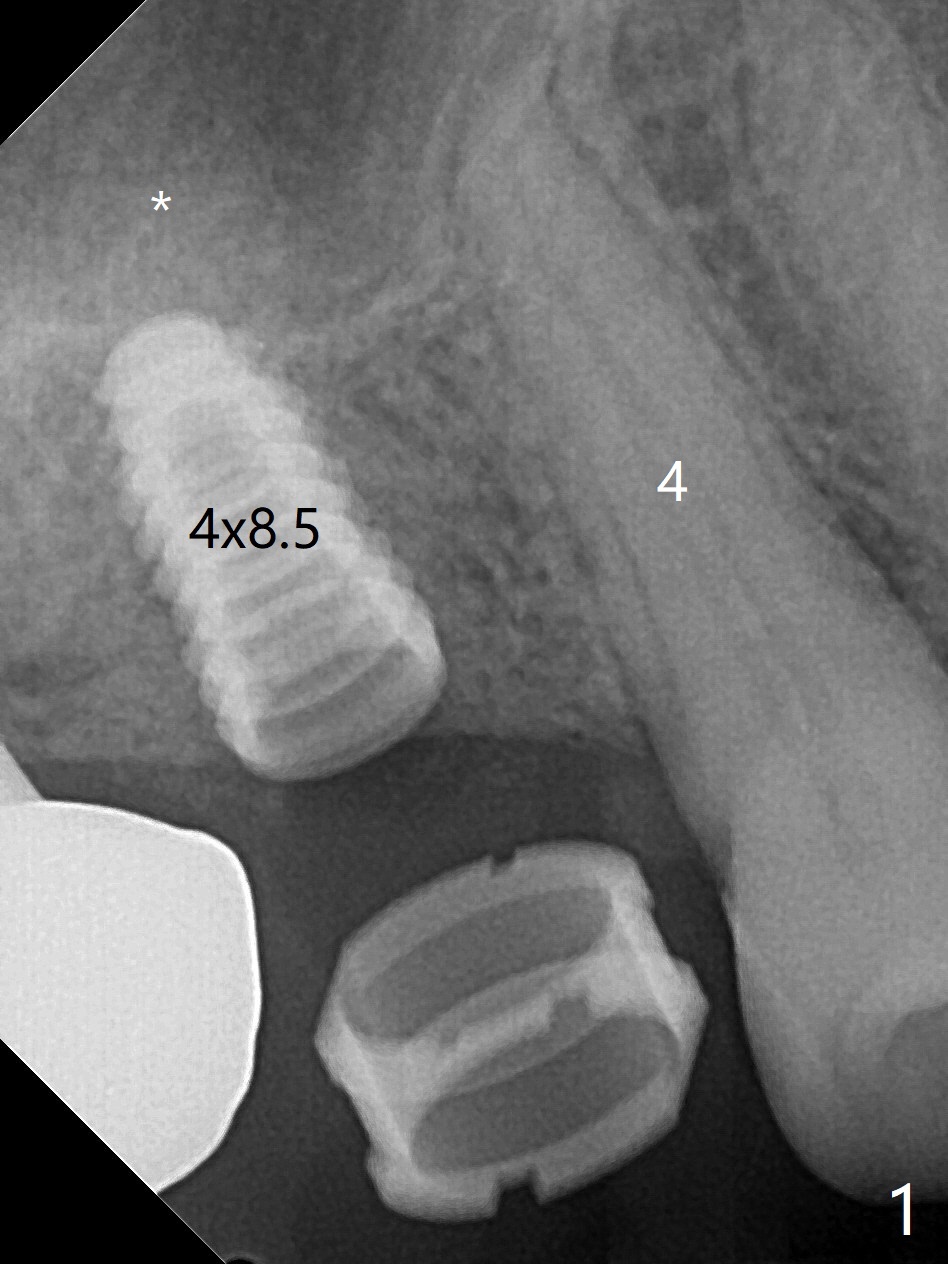

58岁男3号牙位点保存后11个月回来种植,在导板指引下,完成钻洞(3.5x7.3毫米钻头),窦底好像没有破裂,但是仍放置粘性骨粉,使用4x8.5毫米报废植体提升,没有成功。使用2.2x8.5和3.0x8.5毫米钻头,加放骨粉,再次旋入报废植体(大约7.3毫米,图一),骨粉进入上颌窦(*)。使用3.5x8.5毫米钻头后,放置骨粉,植入正式4.5x9毫米(图二,~15Ncm),由于骨扩张,临床检查也证明腭侧(P)不需要植骨,植体周围骨质密度增加。使用5.5毫米Profile钻头(图三:<)后,放置4.5x3毫米愈合基台,PRF膜插入后者和牙龈之间。